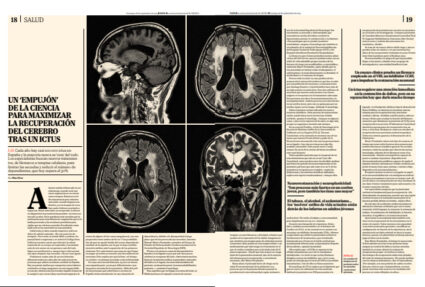

Un «empujón» de la ciencia para maximizar la recuperación del cerebro tras un ictus

Recorte del suplemento Papel de El Mundo